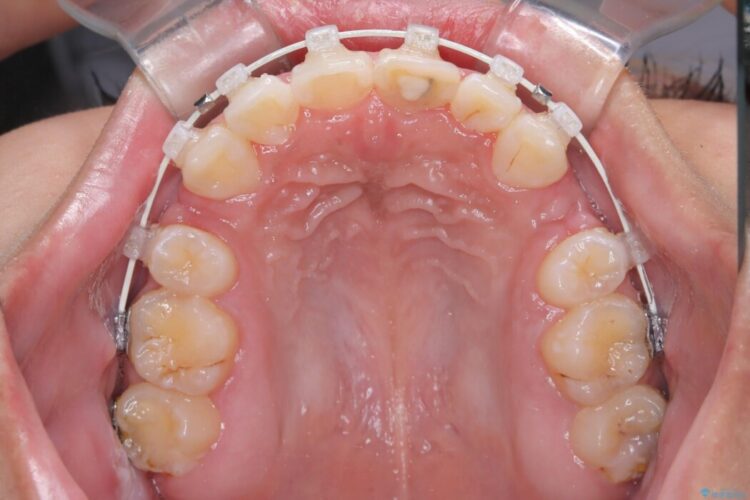

無理に歯を並べても口元の突出感は解消されないため、上下左右4番を抜歯しスペースを確保、目立ちにくい審美ワイヤー装置にて治療を行うこととしました。

抜歯によって得たスペースを活用し、審美ワイヤーによる繊細な角度調整を行いながら前歯を後方へ移動。

突出していた口元のボリュームを段階的に抑制し、理想的なバランスへと導きました。

機能面では上下の緊密な咬合を確立し、審美面ではEラインの劇的な改善を実現しました。 形態と機能の両立により、患者様の満足度が非常に高い仕上がりとなりました。